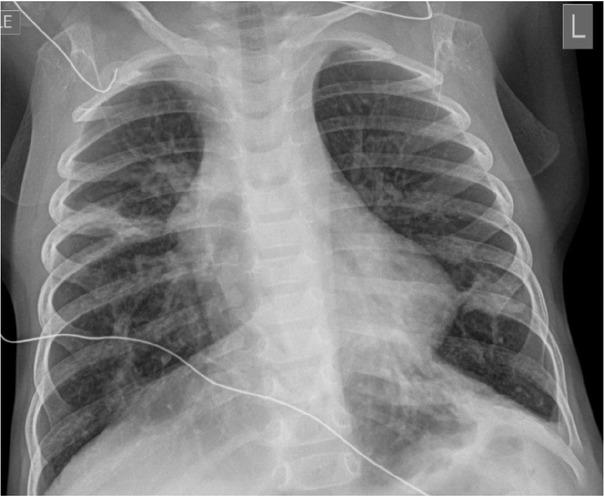

Fig. 1